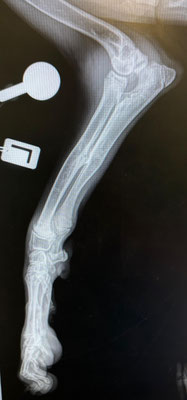

Im September 2025 haben wir Ihnen die kleine Finija vorgestellt: Gerade einmal vier Monate alt, wurde sie in einem erschütternden Zustand gefunden. Beide Hinterbeine waren gebrochen, eine Fortbewegung war für sie nur noch auf den Vorderpfoten möglich. Trotz starker Schmerzen zeigte Finija eine unglaubliche Willenskraft – ein kurzes Video aus…